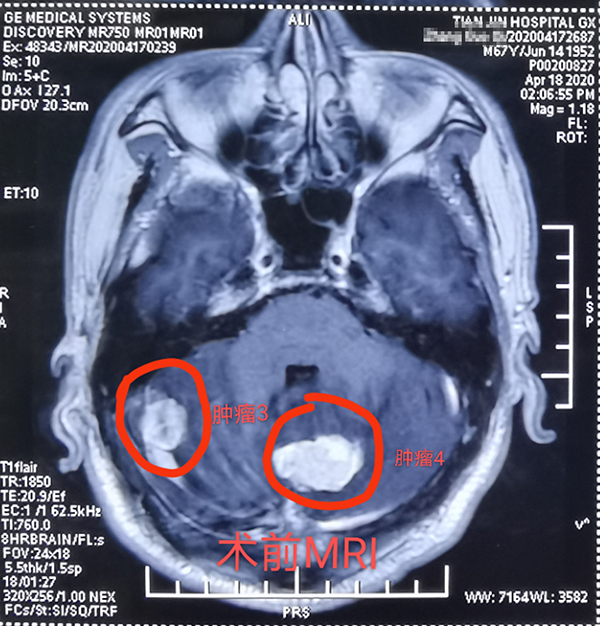

近日,總醫(yī)院神經(jīng)外科成功開(kāi)展1例顱內(nèi)多發(fā)腫瘤切除術(shù),患者為一名67歲男性,半月前因意識(shí)逐漸障礙就診,發(fā)現(xiàn)顱內(nèi)多發(fā)轉(zhuǎn)移瘤,從天津來(lái)我院就診,術(shù)前患者已昏迷,影像科開(kāi)通綠色通道,盡快定位完善檢查、評(píng)估和新冠篩查后,在1次全麻下,2次擺體位,2次鋪單,連續(xù)4個(gè)不同部位先后開(kāi)顱,從前到后,從上到下,從大腦到小腦、從小腦到腦干及竇鐮旁,包括“U”型切口額瓣入路、直切口頂瓣入路、乙狀竇后入路、枕后正中入路,利用顯微鏡神經(jīng)外科技術(shù),切除4個(gè)腫瘤,其中3個(gè)為轉(zhuǎn)移瘤,1個(gè)為腦膜瘤。手術(shù)歷時(shí)12小時(shí),出血約600毫升,術(shù)后患者恢復(fù)良好,8天拆線出院,現(xiàn)已下地行走,生活自理。1期4次開(kāi)顱切除4個(gè)部位腫瘤少有報(bào)道,是對(duì)神外醫(yī)生與手術(shù)室配合程度的考驗(yàn),是對(duì)神外醫(yī)生定位技術(shù)和顯微技術(shù)的考驗(yàn)。通過(guò)多年觀察發(fā)現(xiàn)顱內(nèi)轉(zhuǎn)移瘤,在原發(fā)病灶控制良好的情況下,手術(shù)效果明顯,能較好地提高患者的生活質(zhì)量。